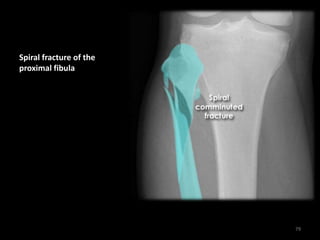

Maisonneuve fracture - AP

proximal tibia-fibula

78

Spiral fracture of the

proximal fibula

79